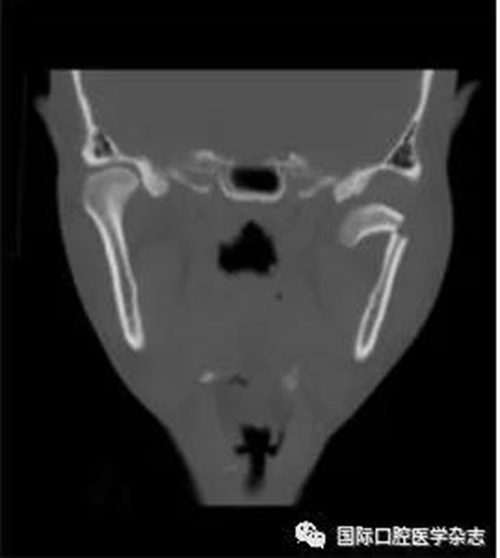

(3)骨關(guān)節(jié)?。▓D2):屬于顳下頜關(guān)節(jié)器質(zhì)性改變,主要發(fā)生在髁突的骨質(zhì)變化,其次是關(guān)節(jié)窩及關(guān)節(jié)結(jié)節(jié)的改變。影像學(xué)檢查發(fā)現(xiàn)骨、軟骨和關(guān)節(jié)盤有退行性改變,關(guān)節(jié)運(yùn)動時可聞及連續(xù)摩擦音。伴有滑膜炎或關(guān)節(jié)囊炎時,有開口痛和咀嚼痛,開口受限,這時可稱骨關(guān)節(jié)炎。

圖 2 骨關(guān)節(jié)病